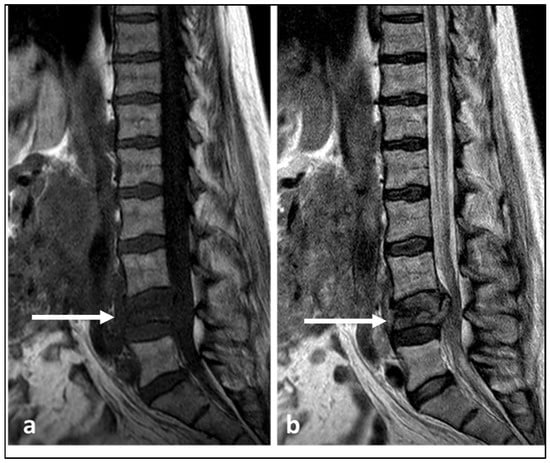

| Chordoma | Low attenuation lytic lesion. | Loculated high T2 signal mass, usually with extra-osseous soft tissue component. High T1 signal due to haemorrhagic and calcified components. |